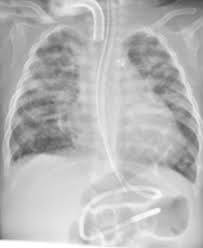

Panitumumab Induced Fatal Ild Chest X Ray On Day 1 Of Admission Download Scientific Diagram

Chest X Ray On Presentation Showing Signs Of Interstitial Lung Disease Download Scientific Diagram